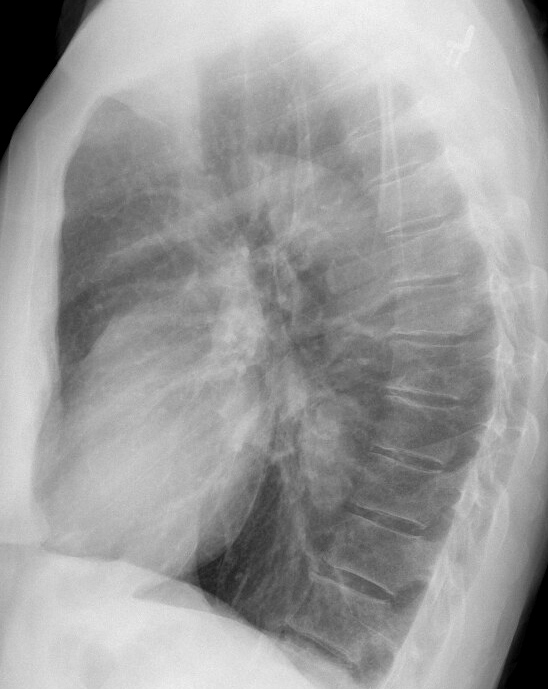

Gallery Mediastinum Lymphoma 8b

8b